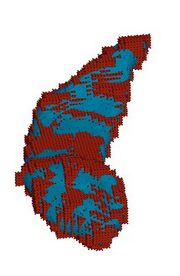

| 02:17, 18 December 2006 | CaseD0688 L dil5 sens1.jpg (file) |  |

52 KB | Image import script | Importing image file | 1 |